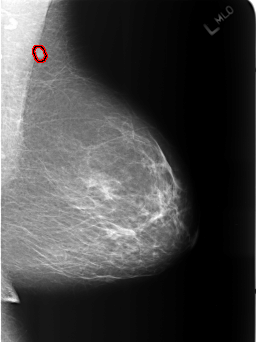

B_3186_1.LEFT_MLO

LEFT_MLO LINES 5464 PIXELS_PER_LINE 4096 BITS_PER_PIXEL 12 RESOLUTION 50 OVERLAY

FILE: B_3186_1.LEFT_MLO.OVERLAY

TOTAL_ABNORMALITIES 1

ABNORMALITY 1

LESION_TYPE MASS SHAPE OVAL MARGINS CIRCUMSCRIBED

ASSESSMENT 2

SUBTLETY 4

PATHOLOGY BENIGN

TOTAL_OUTLINES 1

BOUNDARY